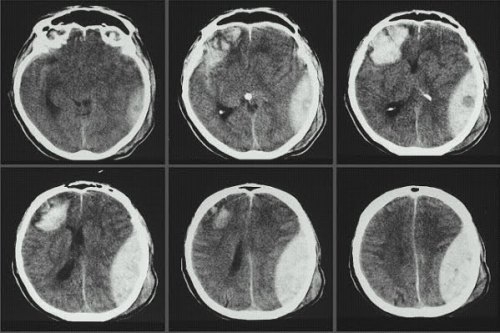

Old  Default Bí ẩn: Sau cú ngã chấn thương sọ não trở thành nhà tiên tri

Ông Peter Van Der Hurkos sau khi bị ngã chấn thương sọ não bất ngờ có năng lực phi thường như tiên tri nhìn thấy trước vận mệnh của mình và người khác.

Những trường hợp nêu trên cho thấy Hurkos có được năng lực tiên tri sau lần bị chấn thương sọ não năm 1941. Tài năng của Hurkos thuyết phục được cảnh sát châu Âu và Mỹ và họ đã mời ông cộng tác.